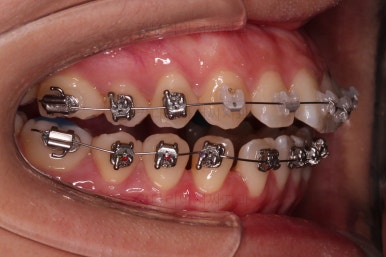

장치를 부착했는데요.

윗니는 웃을 때 더 많이 보이기 때문에 세라믹 장치를 선택하셨고, 아랫니는 거의 안보이는 타입이셔서 메탈장치로 부착을 했습니다.

위아래 둘 다 자가결찰 장치였고요.

우선 가지런하게 하는 작업을 했고요.

교합을 맞춰야 하기 때문에 윗니는 통째로 약간 뒤로 밀어줍니다.

아랫니는 앞니가 더이상 뒤로 들어가지 않도록 어금니를 앞으로 당기는 셋팅을 해줍니다.

그래서 위아래 좌우 모두 다른 용도로 미니스크류가 식립되었고요.

각각의 방향으로 계속 당겨줍니다.